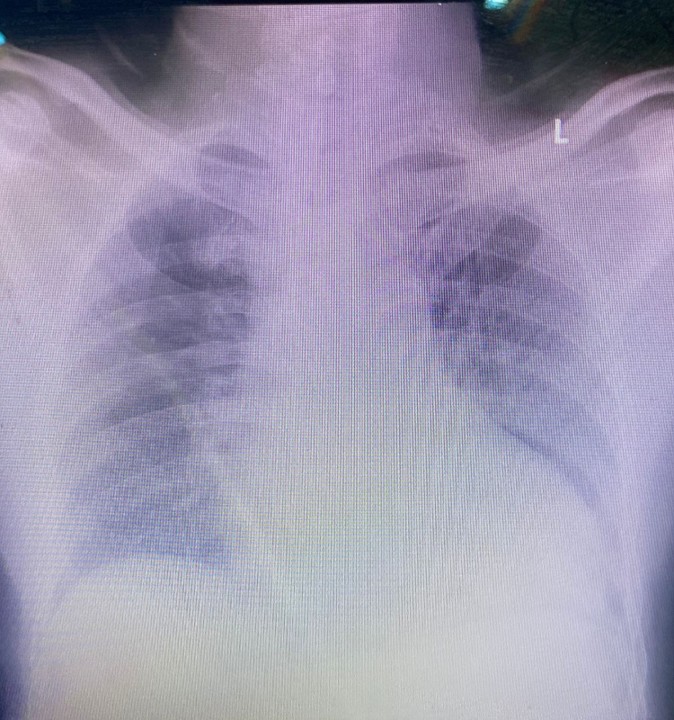

Relevant Test Results Prior to Catheterization

His ECG showed normal sinus rhytmwith poor R wave progression in anterior lead . Before procedure 2 months agothe echocardiography showed reduced LV systolic function with LV ejectionfraction of 32%, recently the ejection fraction was increased to be 46% withregional wall motion abnormalities in LAD teritory. His notable laboratoryfindings were random blood glucose levels of 105 mg/dL, LdL cholesterol 134mg/dL, Creatinine 1.0 mg/dL